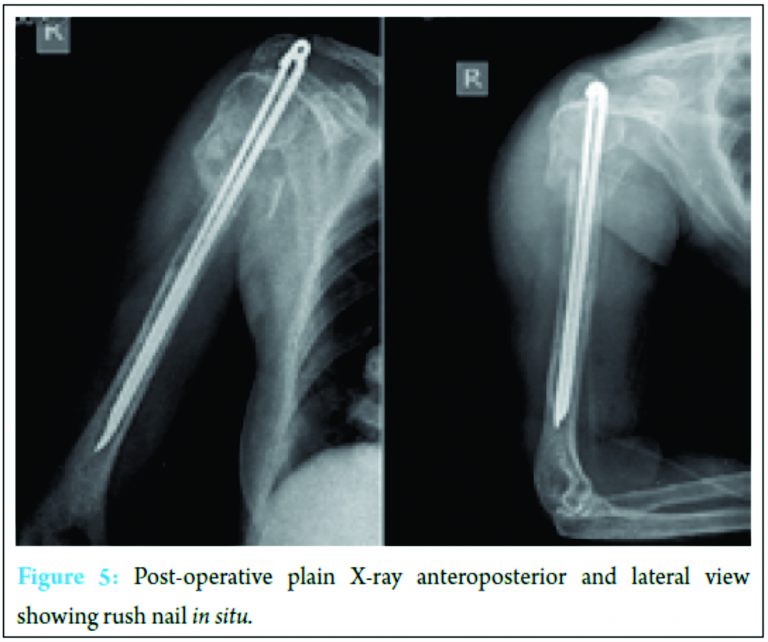

Mantaoux test was negative. Bronchoalveolar lavage was done and sample sent for culture and sensitivity came out to be negative for acid-fast bacilli. Considering tumor and tuberculosis as differential diagnosis, J-needle biopsy was done from anterolateral aspect of proximal humerus at the fracture site. The tissue material obtained from biopsy was sent for histopathological examination which confirmed granuloma with epithelioid and Langhan’s giant cells. Culture for acid-fast bacilli of biopsy tissue sample was non-conclusive. Based on the histopathology report, we concluded this to be tuberculosis osteomyelitis of humerus and our patient was started on category 1 antitubercular drugs, under Revised National Tuberculosis Control Programme (RNTCP) as per revised WHO guidelines. After 3 days of starting antitubercular drugs, debridement of lesion and fracture fixation using rush nail was done. Standard deltopectoral approach was used to explore the lesion. Both intra- and extra-medullary debridement were done. We used reamers for intramedullary debridement. From the edges of lesion, 1 cm of bone was removed. Debridement was done till all necrotic tissue was removed and bleeding was seen from the edges of bone. Fracture ends were approximated and using greater trochanter as entry point, rush nails were inserted (Fig. 5). We did not use any local antibiotic drug delivery method. Procedure was uneventful, stitches were removed on day 14th and incision healed well. Post-operatively, our patient was continued on category 1 antitubercular drugs. Initial follow-up 4 months postoperative and plain radiography after 7 months (Fig. 6) showed overall improvement in general condition of patient, weight gain, and good fracture healing. After 1 year following index surgery, patient complained of pain at nail insertion site at the tip of greater trochanter and shoulder abduction was restricted beyond 40°. The patient did not have pain at fracture site. Rush nails were removed (Fig. 7). Pain subsided following nail removal and shoulder abduction improved with restriction only in terminal 30°. Fracture healed completely, and patient was pain free. Compared to opposite shoulder, abduction and forward flexion were restricted in terminal 30°. Internal and external rotations and adduction were full.

We report a case of tuberculous osteomyelitis of humerus with pathological fracture in a 62-year-old female diabetic. In India, 30-40% of population of all age groups have been found to be infected with tubercle bacilli by different surveys [3]. Overall, skeletal tuberculosis accounts for nearly 5% of all cases of tuberculosis and 18% burden of extrapulmonary tuberculosis [4]. Diagnosis of tuberculosis is difficult due to its indolent course and bizarre clinical findings and radiological presentations. In skeletal tuberculosis, clinical findings are often non-specific and eccentric. Spine and hip remain the most common sites of skeletal tuberculosis [5]. Involvement of long bones is rare and we could not find any report of humerus diaphyseal tuberculous osteomyelitis presenting with pathological fracture without joint involvement. The exact incidence of isolated humerus tubercular osteomyelitis is not known. Skeletal lesions are secondary to some primary foci in lungs or viscera which may be active or quiescent.The lesions are often result of hematogenous spread from distant site primarily lung [6]. There have been reports of tubercular osteomyelitis of maxilla [7], cervical vertebra [8], spontaneous ulna fracture [9], sternum [10], clavicle [11], femur [12], and shoulder joint with fracture dislocation [2] but no reports on proximal humerus diaphyseal tuberculosis without shoulder joint involvement causing pathological fracture. Mangwani et al. in 2001 in their study have emphasized that tuberculosis can involve shoulder joint with humerus leading to fracture-dislocation [2]. In their patient, probably shoulder joint was involved first, and during the fulminant course, infection involved periarticular surface and then osteomyelitis of bone per se leading to fracture dislocation of humerus. However, in our patient, articular space was normal and lesion was in diaphysis of humerus, 5 cm distal to surgical neck. To the best of our knowledge, this is the first well-documented case of proximal humerus diaphyseal tuberculous osteomyelitis without articular involvement presenting with pathological fracture. In one study, Herzog pointed out varied presentation of multiple osteolytic compression fractures of cervical spine in treated case of acute lymphatic T-cell leukemia. Even after induction chemotherapy, the lesions did not resolve and subsequently they termed it as chronic recurrent multilocular osteomyelitis before documenting mycobacterium from intra-abdominal abscess [13]. Mohideen et al. in 2013 in their study on tuberculosis in hip region have reported tuberculosis presenting as permeative lesion in femur metaphysic along with bony erosion; however, the same report has emphasized that permeative lesion and radiological appearance of periosteal reaction are very rare entity in osteoarticular tuberculosis [14]. In ulna fracture, drainage of cold abscess and excision of necrotic bone with immobilization in plaster resulted in full recovery though in osteomyelitis of maxilla, antitubercular treatment sufficed [6,8]. We screened our patient for multiple myeloma and plasmacytosis. In our case, treatment options were either debridement followed by definitive fixation, external fixator, or non-operative. But considering the pathology, we decided to do open debridement. We did not used external fixator as the patient was staying in remote area and follow-up at regular interval was doubtful. We could not find any guidelines for management of such pathological fracture. We did J-needle biopsy and histopathological examination of biopsy specimen to confirm the diagnosis followed by debridement and fixation with rush nails (Fig. 5). Our patient was started preoperatively on antitubercular drug regimen, category 1 under RNTCP as per the WHO guidelines for management of tuberculosis. The lesion healed completely (Fig. 7) and rush nails were removed 1 year after index surgery due to pain. Patient gained weight and had overall improvement in clinical findings.